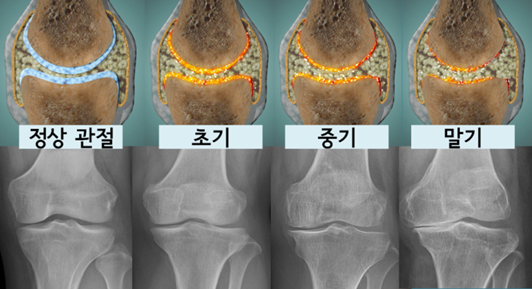

도식도로 보면 다음과 같습니다.